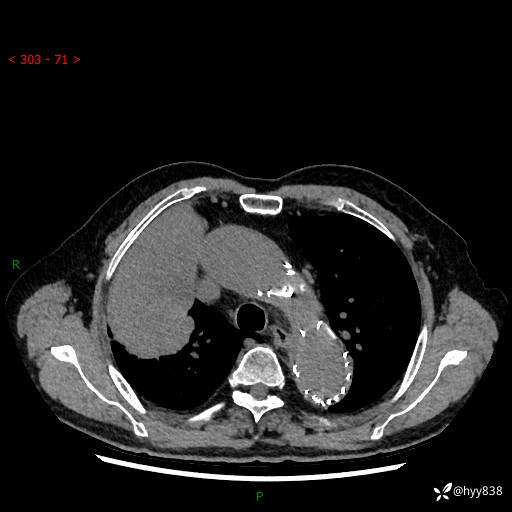

辅助检查:CT

胸部CT平扫